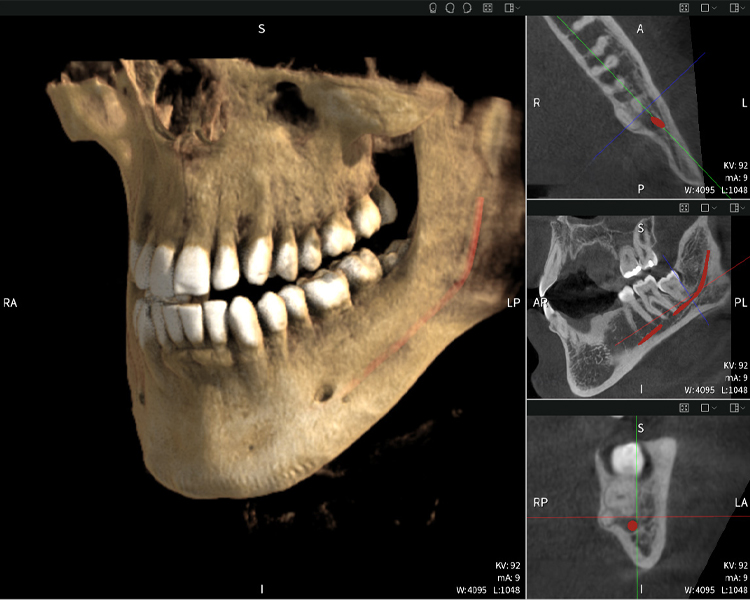

Below you will find a case from Dr. med. dent. Oliver A. Centrella, in which the CBCT images obtained with Seethrough Max provided crucial information on the complex anatomy and the critical relationship between the wisdom teeth and the inferior alveolar nerve. In this case, there is a indication for the surgical removal of the wisdom teeth.

Figure a

- Top left: Axial cross-section of the left mandible (region 38) showing the inferior alveolar nerve (red) in proximity to the roots of tooth 38.

- Top right: 3D reconstruction of the entire mandible for orientation. The red-marked inferior alveolar nerve illustrates its location within the jawbone.

- Bottom left: Sagittal view of the mandible (region 38), highlighting the close spatial relationship between the roots and the nerve canal.

- Bottom right: Coronal view of the mandible (region 38), which is crucial for assessing the spatial position of the roots relative to the nerve.

Figures b–d show various views of a 3D reconstruction of the mandible, providing a comprehensive overview of the mandibular anatomy, the position of the nerves in relation to the teeth, and allowing assessment of tooth symmetry and alignment.

Figure d shows the previously treated tooth 48, with its crown removed, and its roots left in proximity to the nerve, illustrating the high risk of nerve damage.